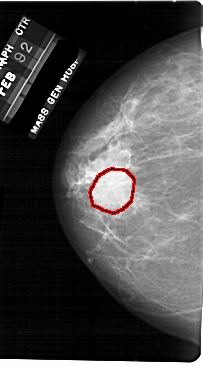

FILE: A_1710_1.LEFT_CC.OVERLAY

TOTAL_ABNORMALITIES 1

ABNORMALITY 1

LESION_TYPE MASS SHAPE ROUND MARGINS OBSCURED

ASSESSMENT 3

SUBTLETY 5

PATHOLOGY BENIGN

TOTAL_OUTLINES 1

BOUNDARY